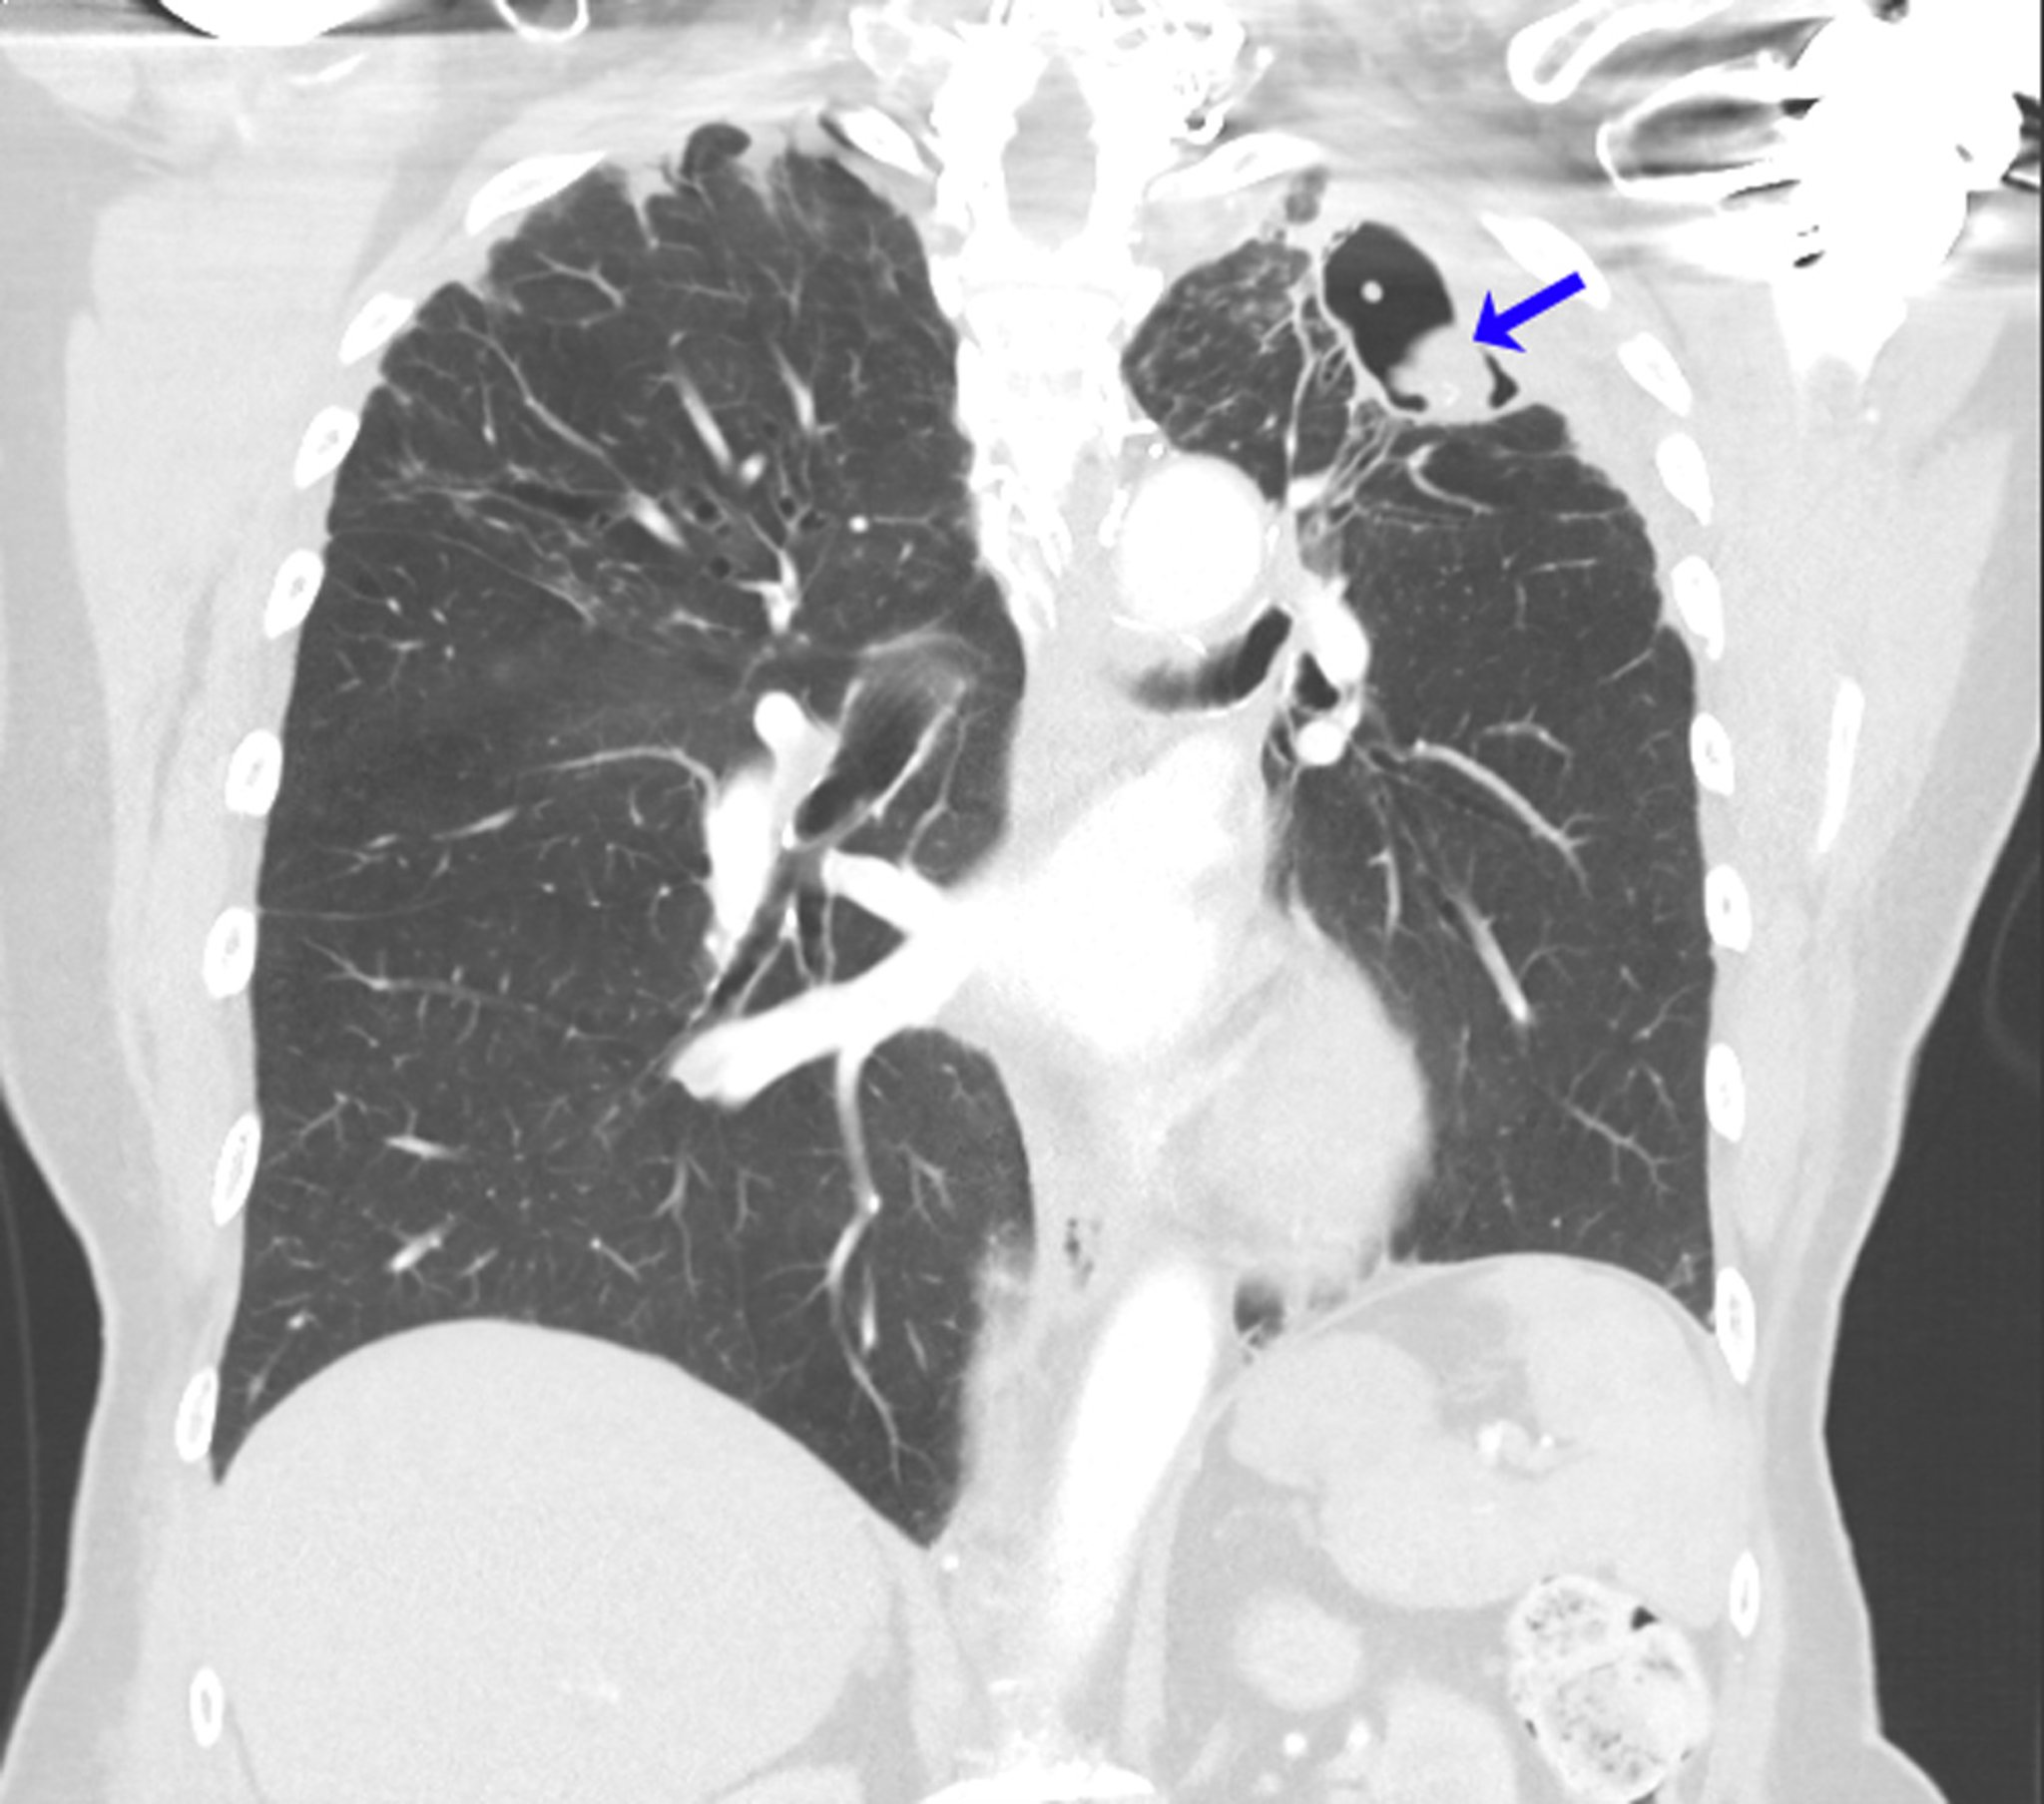

Aspergiloma recidivante

Esta TC muestra los pulmones de una persona con antecedentes de aspergilosis broncopulmonar alérgica en el contexto de asma. Después de la lobulectomía superior izquierda para el aspergiloma, se desarrolló un micetoma recurrente en el vértice pulmonar izquierdo (flecha).

Image courtesy of Paschalis Vergidis, MD, MSc.